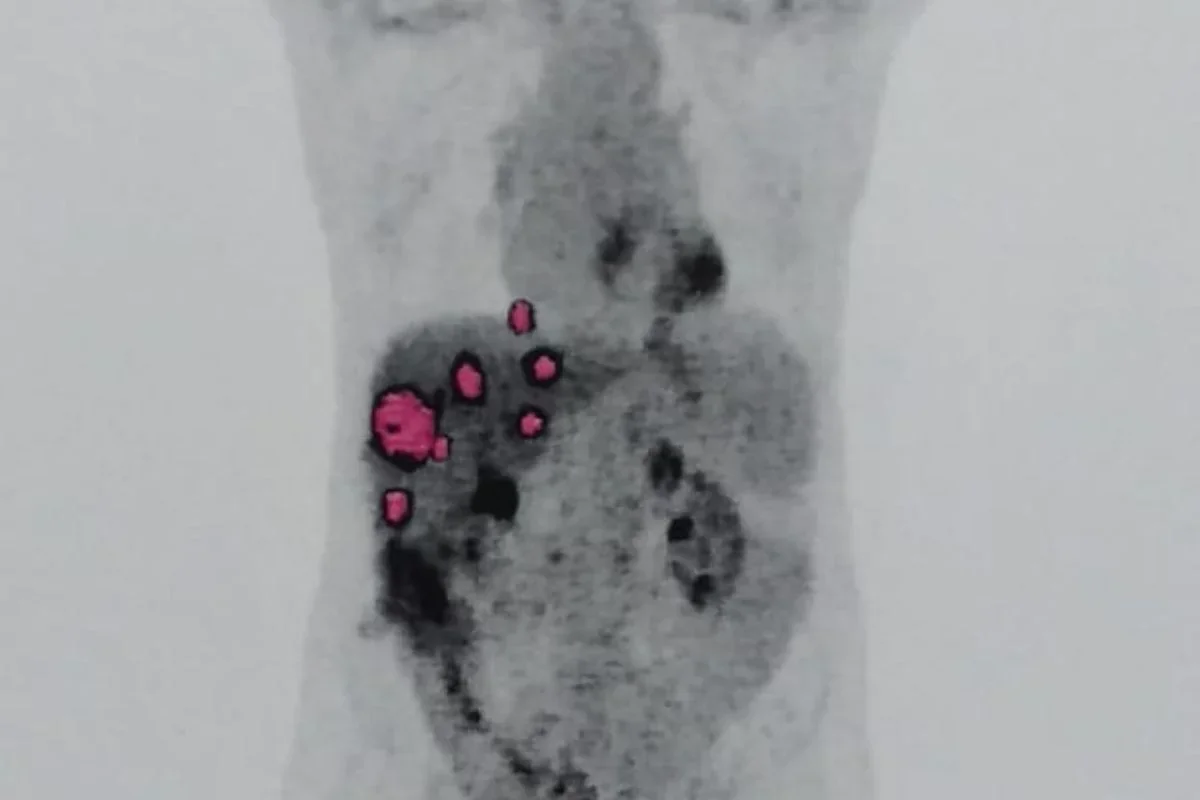

Geraldo Vaz Junior, de 58 anos, passou por um transplante de fígado em março de 2023, acreditando que seria o início de uma nova fase após enfrentar a hepatite C. No entanto, meses depois, exames revelaram que o órgão transplantado continha um adenocarcinoma, um tipo de tumor maligno. Pouco tempo depois, ele foi diagnosticado com metástase pulmonar do mesmo câncer.

Especialistas afirmam que a transmissão de câncer em transplantes é extremamente rara, com incidência inferior a 0,03%, mas que o risco existe. O oncologista Paulo Hoff explicou que, apesar da triagem, tumores ocultos podem passar despercebidos. Segundo ele, o câncer veio do fígado transplantado, indicando que a doadora teve a doença em algum momento.